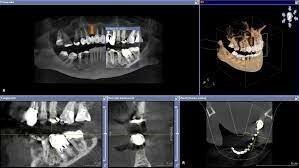

• Hounsfield (1972)

Hounsfield (1972)

En 1972, el británico Hounsfield presenta en Londres el primer tomógrafo computarizado, en el cual la imagen no es analógica, como en la radiología convencional, sino digital.